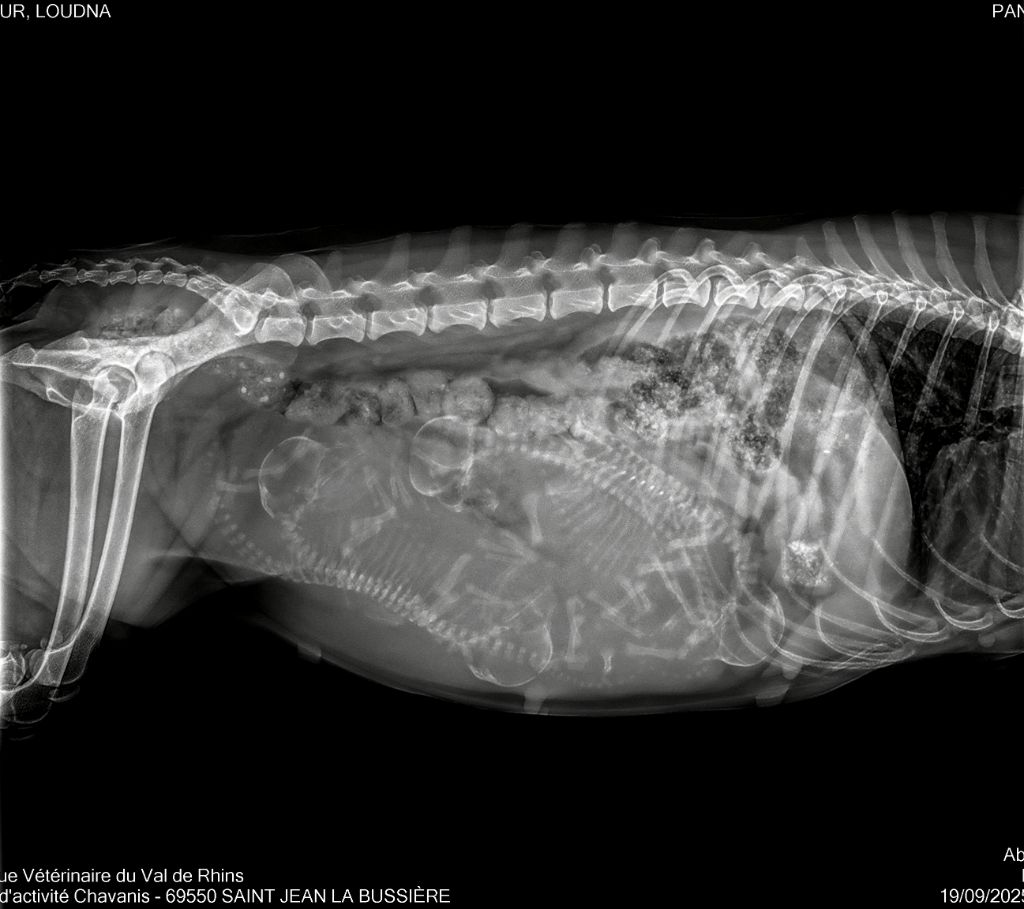

Litter "A" 23/09/2025 Présentation de la portée "A" née le 23/09/25 Radiographie de comptage Naissance de 4 filles le 23/09/25 Azumi - 5 jours Akiko - 5 jours Atsuru - 5 jours Aruna - 5 jours 11 jours 11 jours Azumi - 21 jours Akiko - 21 jours Atsuru - 21 jours Aruna - 21 jours Azumi - 21 jours Akiko - 21 jours Atsuru - 21 jours Aruna - 21 jours Azumi - 1 mois Akiko - 1 mois Atsuru - 1 mois Aruna - 1 mois Atsuru - 5 semaines Aruna - 5 semaines Azumi - 5 semaines Akiko - 5 semaines Azumi - 7 semaines Akiko - 7 semaines Atsuru - 7 semaines Aruna - 7 semaines Akiko - 8 semaines Aruna renommée Alaska - 8 semaines Atsuru renommée Amélie - 8 semaines Azumi renommée A'Suki - 8 semaines Akiko - 8 semaines Amélie - 8 semaines Alaska - 8 semaines A'Suki - 8 semaines Amélie - 9,5 semaines Akiko - 9,5 semaines A'Suki - 9,5 semaines Alaska - 9,5 semaines Amélie - 9,5 semaines Akiko - 9,5 semaines A'Suki - 9,5 semaines Alaska - 9,5 semaines Amélie - 11 semaines Alaska - 11 semaines Alaska - 15 semaines